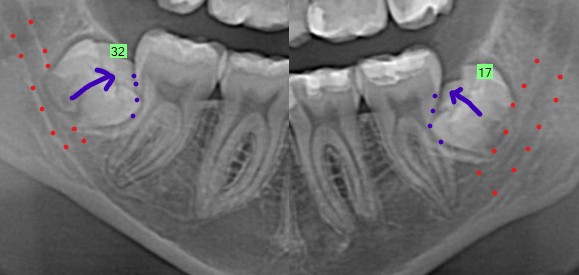

Lower Wisdom Teeth

The lower wisdom teeth (#17,32) are still in early stages of development. Wisdom teeth are generally recommended for removal in teenagers when the roots are 50-75% developed – these wisdom teeth are at about 0% root development. However further root development in this patient will lead to an increased risk of nerve injury (nerve outlined with red dots) if the teeth need to be removed in the future. In addition, the teeth are slightly angled towards the teeth in front, so they have a higher risk of damage to these neighboring teeth through root resorption (purple dots). Due to the increased risk of nerve injury with further root development, this patient was strongly recommended to have both lower wisdom teeth removed. Sometimes, we recommend getting a dental CT scan to evaluate the relationship of the wisdom tooth and the nerve in 3 dimensions. However, I did not require this patient to get as it was not going change the treatment recommended or provided to the patient. Lower wisdom teeth removal can also put pressure in the TMJ. However since the roots are not developed and bone in younger patients tends to be softer, removal will result in less pressure placed on the joints during tooth removal.